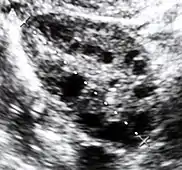

Ultrasound of a polycystic ovary. Each of the dark circles represents a fluid-filled cyst.

Polycystic ovary syndrome (PCOS) is an endocrine disorder characterized by an excess of androgens produced by the ovaries. It is estimated that approximately 90% of women with PCOS demonstrate hypersecretion of these hormones.[18] The cause of this condition is unknown. Speculations include genetic predisposition; however, the gene or genes responsible for this remain unidentified.[19] The condition may have a hereditary basis. Other possible causes include elevated insulin production. Most cases of PCOS involve insulin resistance.[20] It is thought that adipose tissue dysfunction plays a role in the insulin resistance seen in PCOS.[20] Insulin can induce excess testosterone secretion from the ovaries.[21] A complication associated with polycystic ovary syndrome is high cholesterol, which is treated with statins. In a meta-analysis, atorvastatin was shown to decrease androgen concentrations in people with hyperandrogenism.[22]